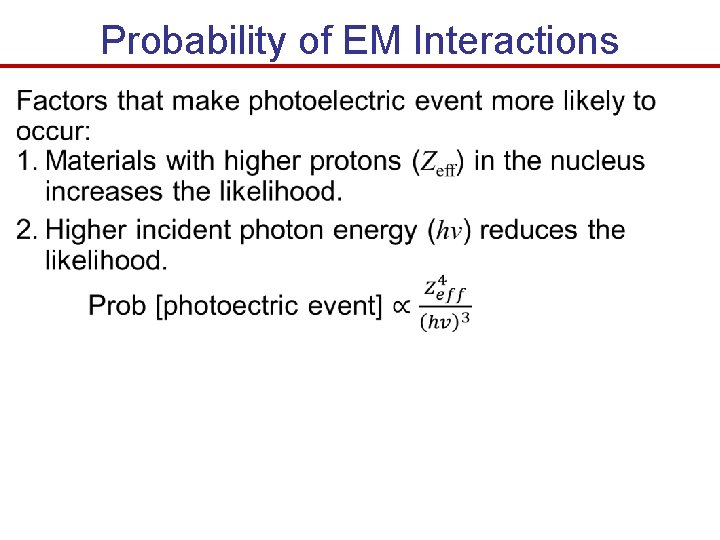

Probability of EM Interactions

Probability of EM Interactions

Relative Frequency of Occurrence Relative frequency of occurrence of photoelectric and Compton events Photoelectric events deposit all of their incident photon energy, while Compton events deposit only a fraction of their incident photon energy At 60 ke. V radiation, 93% of the interactions is Compton but account for only 55% of the energy deposited in the tissue. Explain